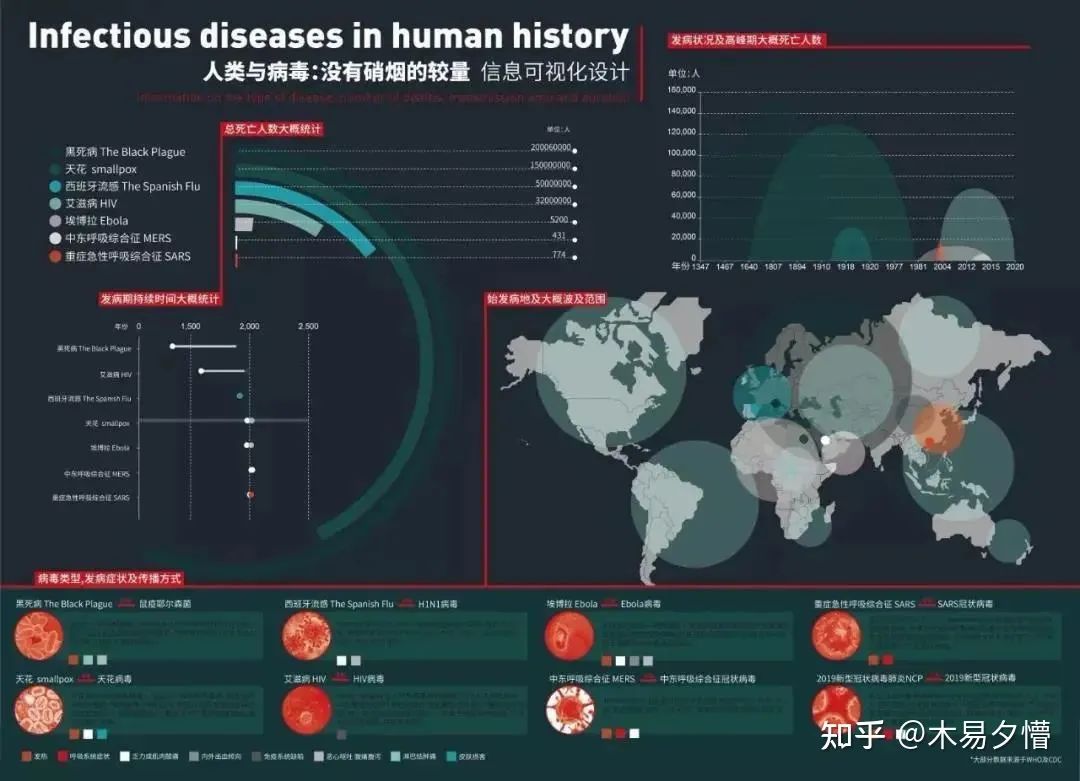

《人类与病毒:没有硝烟的较量》

作者:潘玥 | 南京艺术学院设计学院

这个信息设计作品收集整合了人类历史上几次较有代表性的几次传染病时间的数据,并且从死亡人数、持续时间、波及范围等角度做了信息可视化呈现。漫漫历史长河,人类经历的灾难数不胜数。但于自然面前如此渺小的我们,却每次都凭着顽强的意志和拼搏的精神坚持下来。近日疫情爆发,相信我们一定会团结一心众志成城战胜疫情。武汉加油!中国加油!